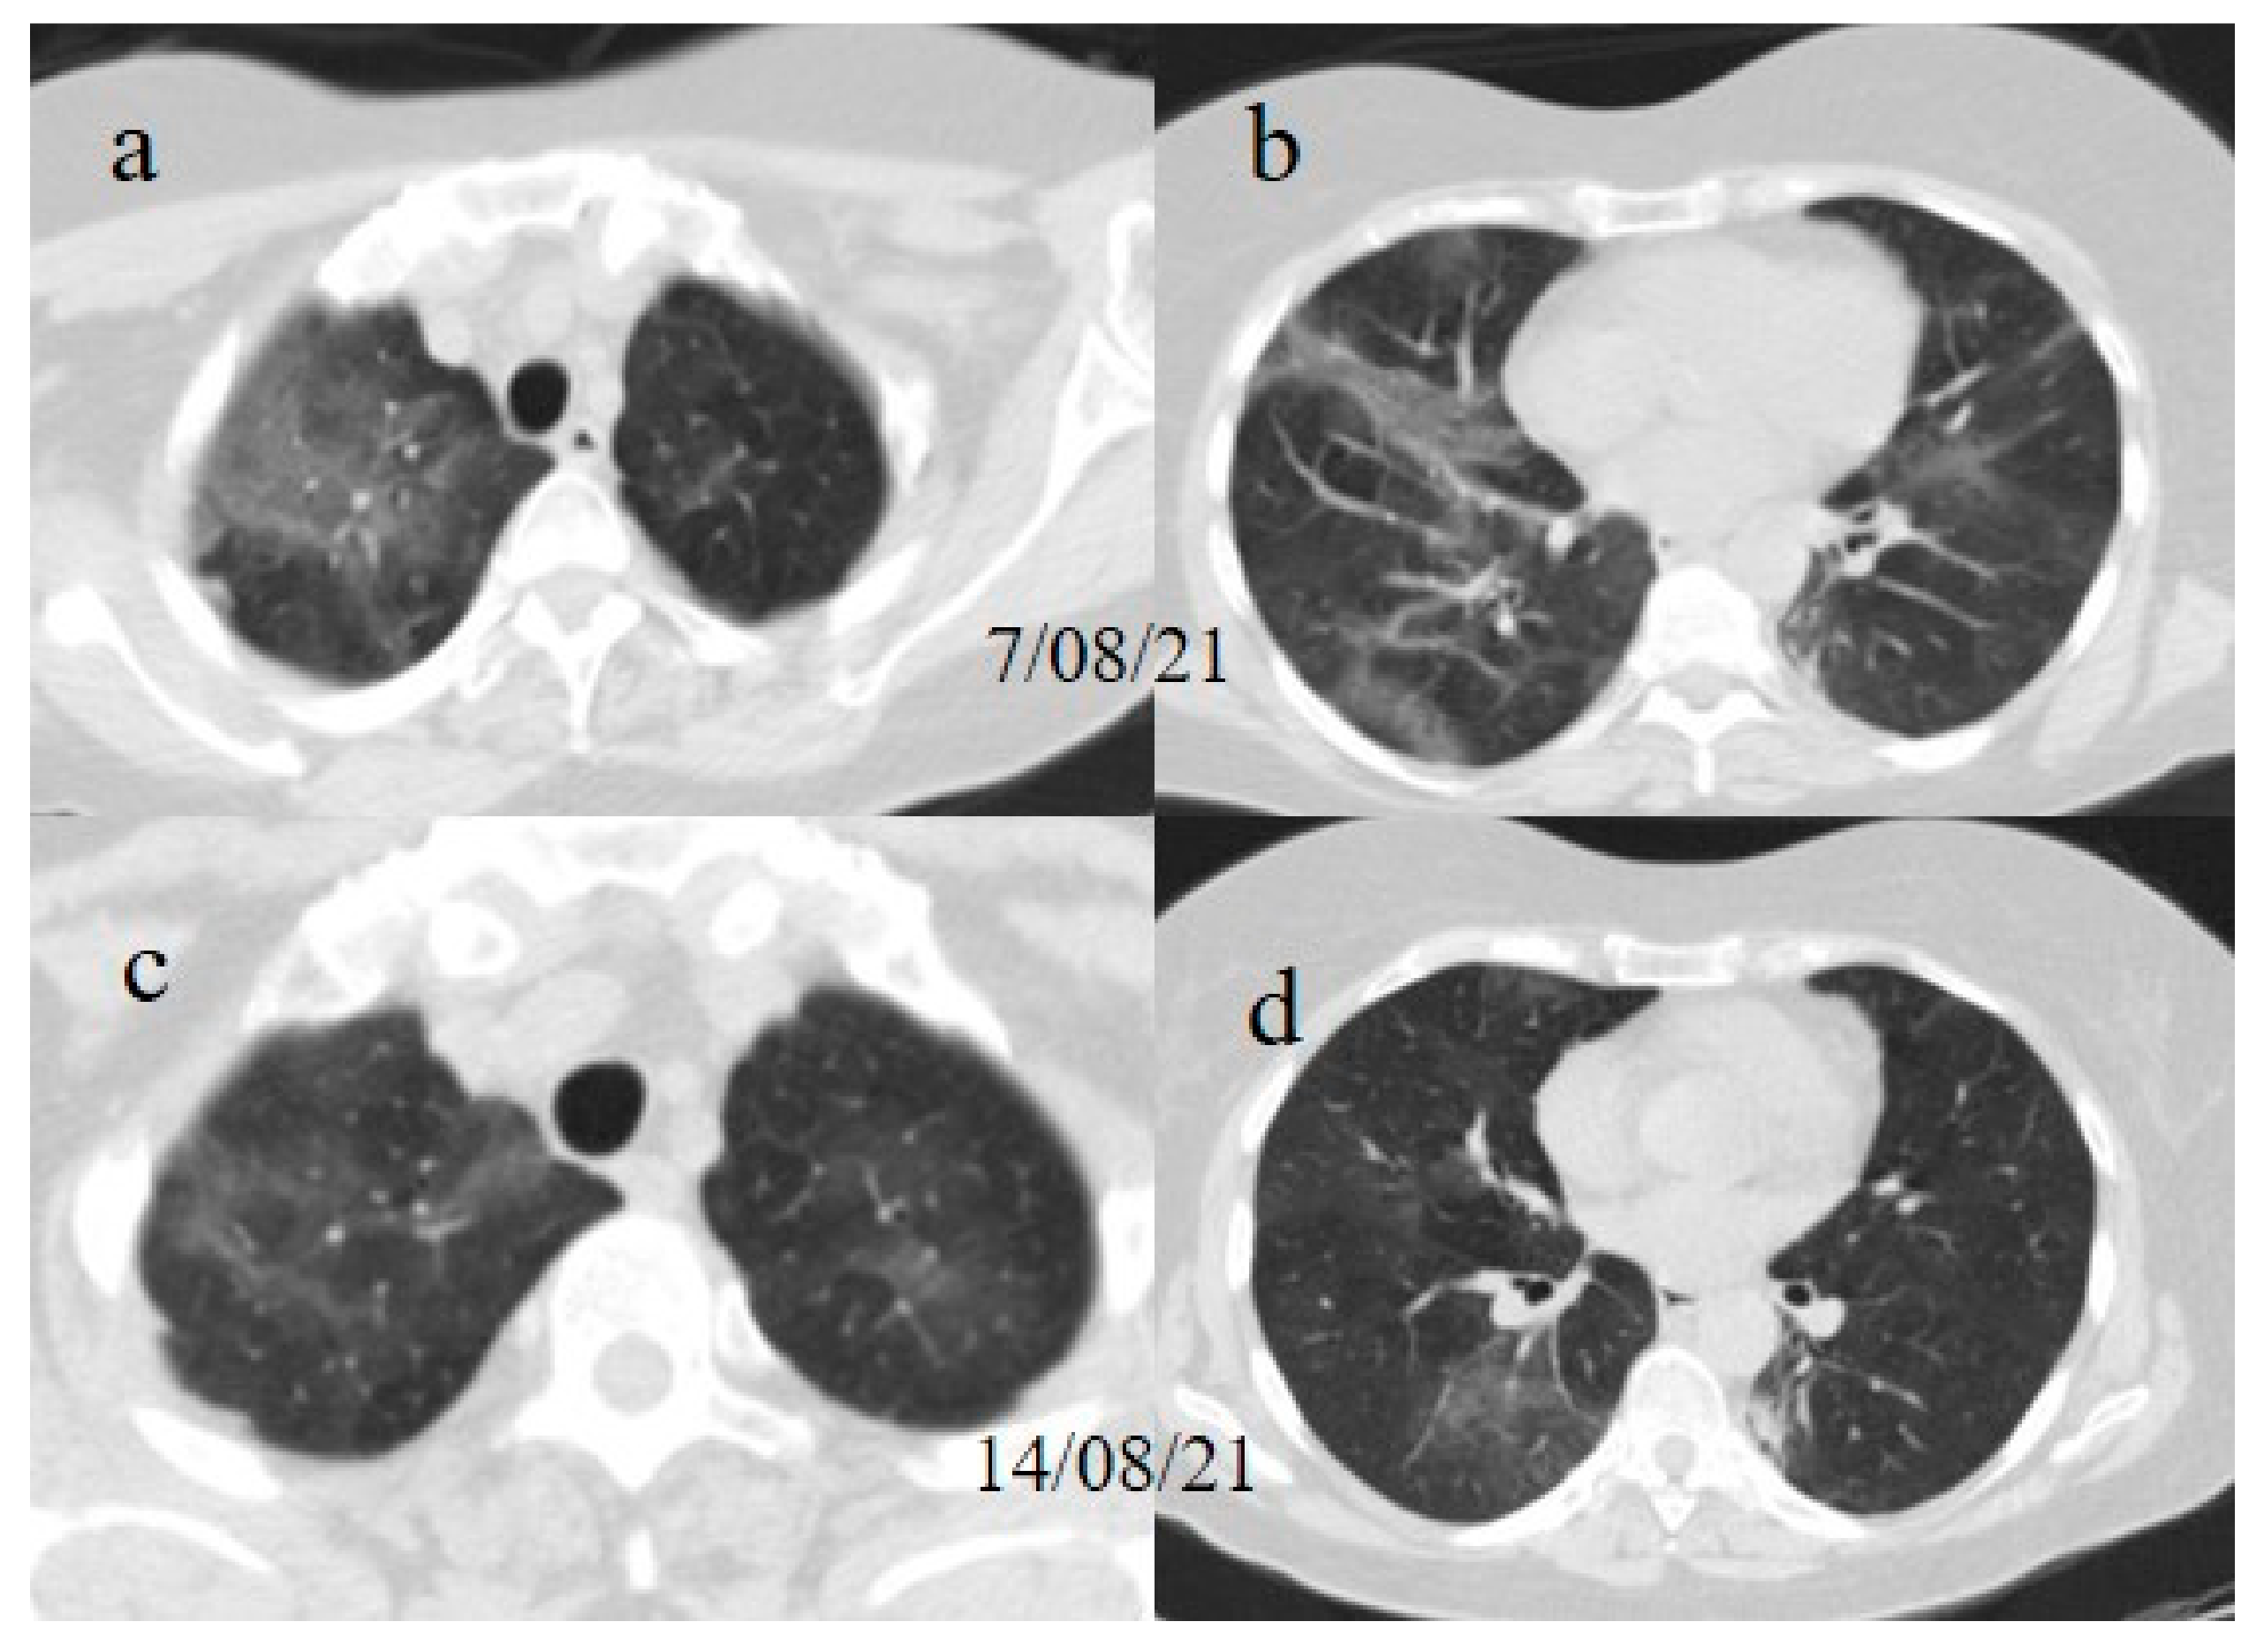

A chest Computed tomography (CT) performed in the emergency department showed a typical central and peripheral distribution of ground-glass opacity (GGO) COVID-19 pneumonia. The CT-SS score [21] showed a value of 13/20 (Figure 1).

One week later (on 9 July), another chest CT was performed due to the worsening of the patient’s symptoms with SO2 at 76% and PO2/FiO2 190.

The chest CT showed extended pneumonia, with an evolution in a crazy paving pattern and consolidation areas (CT-SS 16/20) (Figure 1). The patient died 5 days later.

Figure 1. (a,b) The basal CT with GGO in a typical peripheral and posterior distribution of COVID-19 pneumonia with a CT-SS of 13/20. (c,d) The chest CT performed 1 week later, showing more extensive pneumonia with a CT-SS of 16/20.